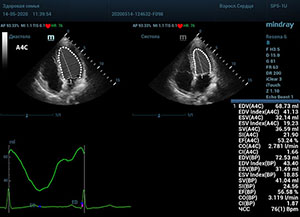

С появлением В режима реализовалась возможность визуализации всех сегментов миокарда из парастернальных и апикальных сечений. Метод Teicholtz в широкой практике сменился методом дисков. Метод дисков, или метод Simpson, позволяет разбить левый желудочек на 20 дисков, с расчетом объема каждого из них. Используя 2 перпендикулярных сечения, апикальные двух и четырех камерное, мы приближаемся к значению реального объема левого желудочка. Исследователь обводит интерфейс эндокард – кровь в фазу диастолы и фазу систолы. Линия простирается от кольца митрального клапана и до кольца митрального клапана, четко разграничивая объем желудочка от предсердия. Для достоверного изменения необходимо использовать ЭКГ канал.

Обводить вручную эти линии занимало много времени, однако результат того стоил. Следующим шагом стало появление Spline технологии, позволяющее расставлять точки и автоматически их соединять. Такой способ планиметрии контура эндокарда значительно сократил время измерения.

Что могут предложить современные приборы? Приборы нашего времени являются мощными вычислительными машинами, способными обрабатывать полученную информацию даже без помощи человека. Система автоматического вычисления фракции выброса – AUTO EF на

приборах серии Resona компании Mindray сделает все за вас. За пару секунд прибор сам отыщет нужную фазу сердечного цикла и произведёт измерение и расчеты, а также покажет график изменения объема в сердечном цикле. От Вас требуется только получить качественное 4С и 2С сечение. Впрочем, прибор всегда оставляет возможность коррекции, если доктор имеет свое мнение на расположение точек планиметрии или момента измерения по ЭКГ каналу.